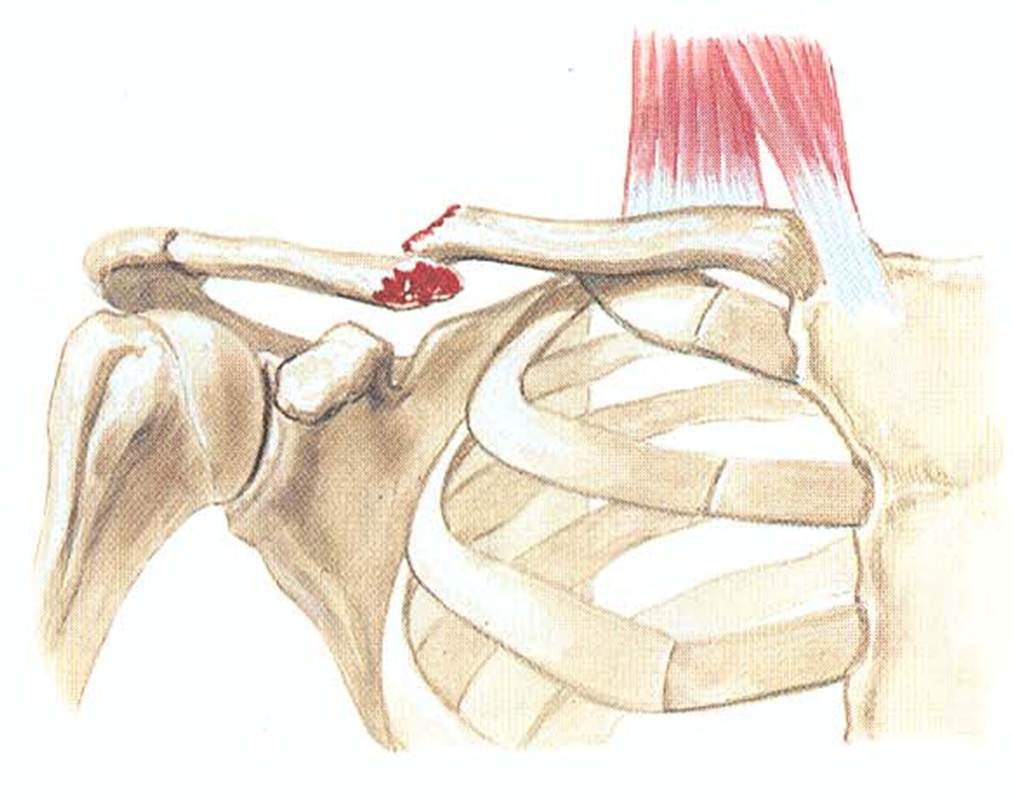

Вывихи и переломы ключицы презентация - 85 фото